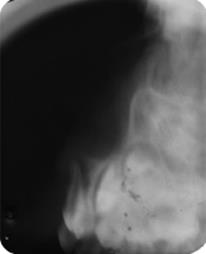

Radiographically, (modified periapical anterior and Fazzi’s lateral radiograph), teeth #61 and #62, without fracture of the bone plate and injury to the germs of

the permanent teeth (Figures 1B and 2). The treatment of choice was to wait for spontaneous teeth re-eruption.

Radiographic examination is also essential in cases of dental trauma involving the supporting tissues, to assess the root condition, the relationship with adjacent structures and the existence of periapical lesions, bone fragments and foreign bodies. The most used radiographic techniques in intrusive dislocations are modified anterior periapical and Fazzi's lateral, which make it possible to evaluate the direction of tooth palatine or buccal displacement24.